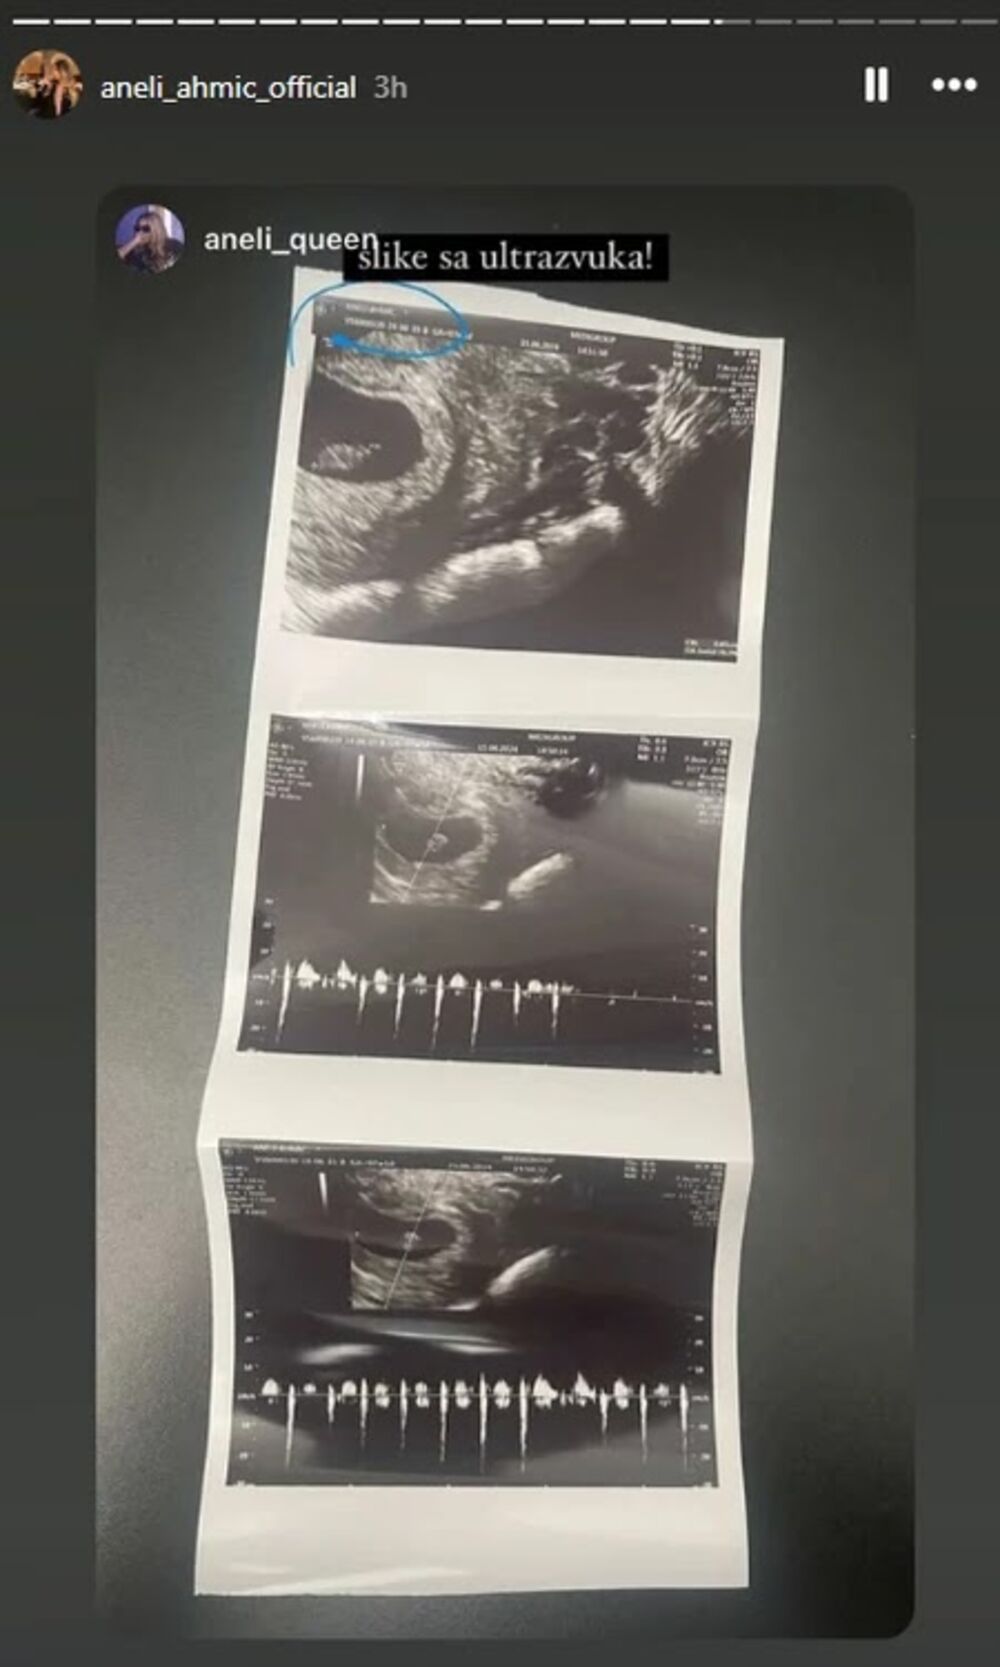

Naime, Aneli Ahmić je danas na prvom pregledu saznala da je trudna šest nedelja, što znači da je u drugom mesecu, a sada su na njenom profilu na Instagramu osvanule slike ultrazvuka, kao i izveštaj sa lekarskog pregleda.

"Da začepimo svima usta. Tražili ste slike sa ultrazvuka i papir da vidite. Izvolite, dosta mi je više ljudi koji govore da je lažna trudnoća" - pisalo je u objavi.